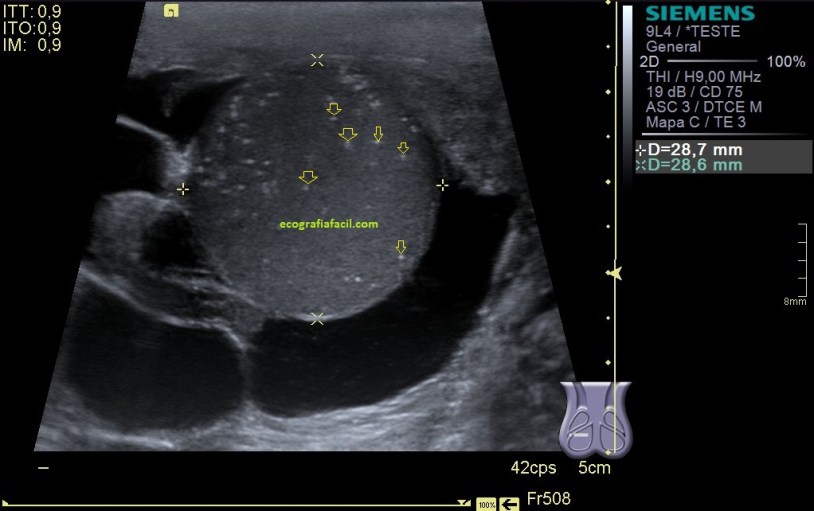

En la imagen 5 podemos ver afectación testícular de las mismas características ecográficas, pero existen varios focos de lesión. imágenes 4 y 5 son pacientes distintos.

El aspecto de esta lesión, su semiología ya la has visto en estos dos casos diferentes, pero tienen en común, de modo general, hipoecogenicidad, heterogenicidad, bordes irregulares, con aspecto polilobulado y de tamaño y número variable.